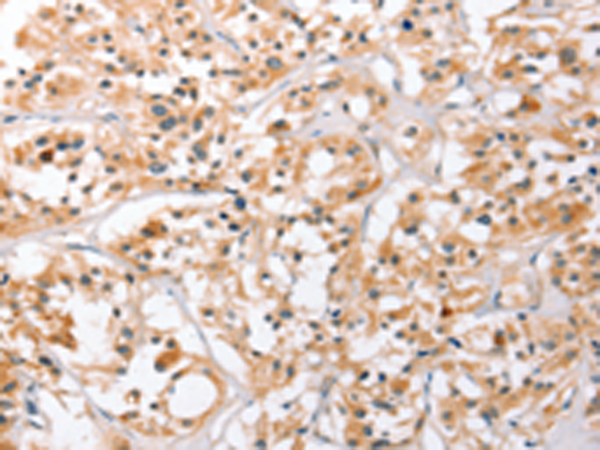

分类: 科研抗体货号: P07331别名: ECGP; GP96; TRA1; GRP94应用: WB,IHC反应种属: Human, Mouse, Rat